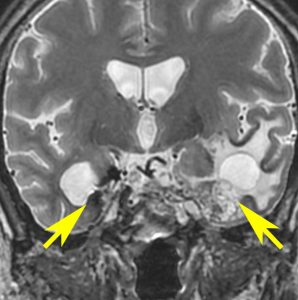

頭蓋底の脊索腫再発のために炭素イオン線 60グレイ16分割の治療を受けました。5年後に両側の側頭葉の脳壊死が生じました。そのために高度の高次脳機能障害となりました。両側の海馬(黄色い矢印)の壊死のために記憶が全くできません。でもしかし,この患者さんは重粒子線治療を受けなければ腫瘍再発で亡くなっていたと私は考えています

左内頸動脈が炭素線被爆したために閉塞しています。

重粒子線は高度の悪性腫瘍をやっつける強力な治療である反面,このように脳や動脈が被爆すればその組織も破壊されてしまいます。悪性腫瘍を破壊できる強力な粒子線治療は,その周囲の神経組織もかまわず破壊する治療であるとも言えます。